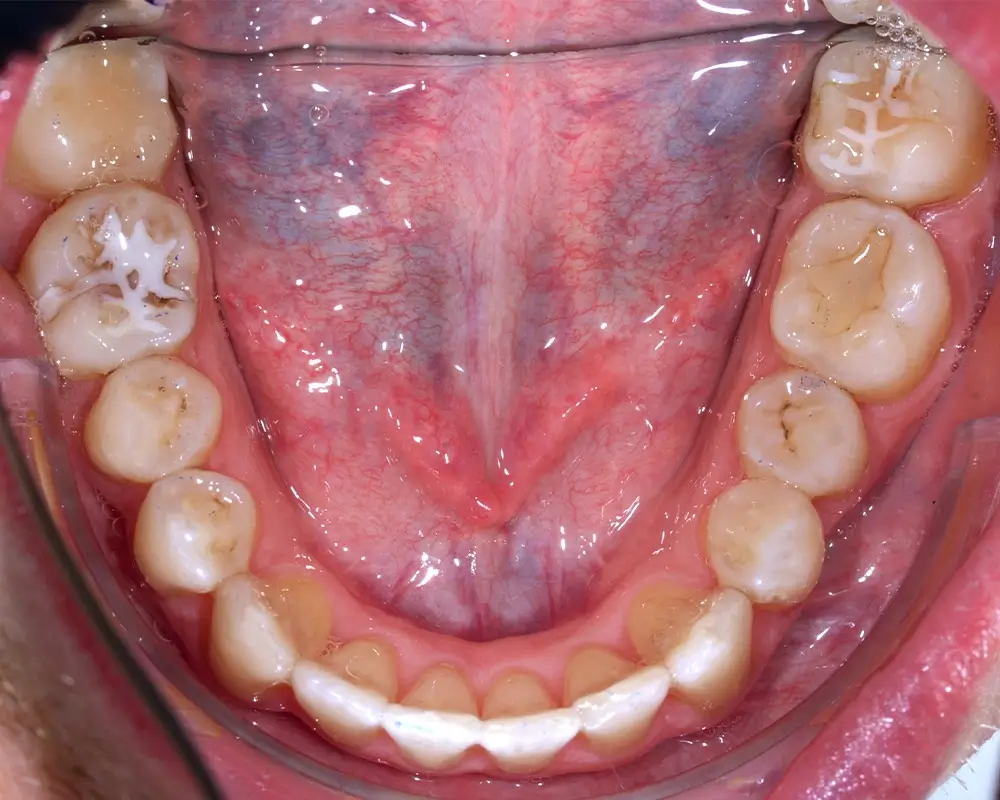

Кейс 4

Бажанова Ольга Валерьевна

Количество кап ВЧ 35

Количество кап НЧ 35

ДО

ПОСЛЕ